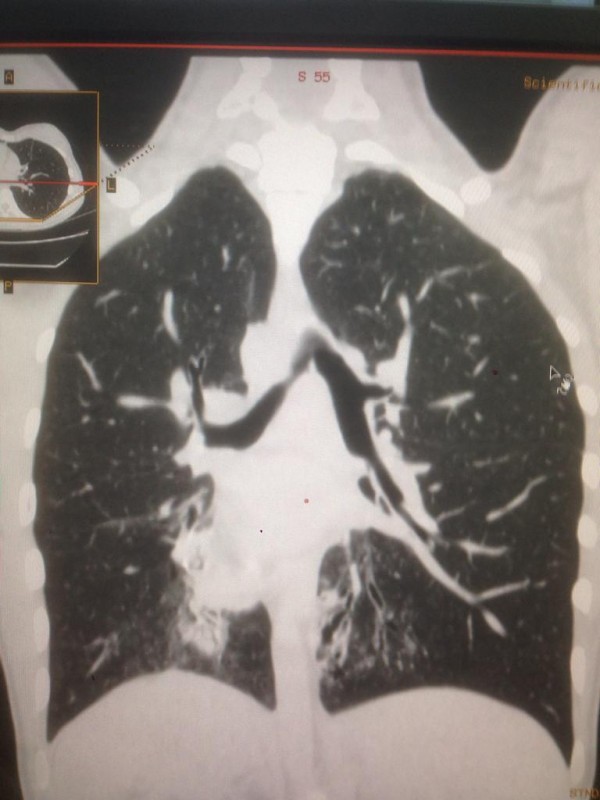

Транспозиция внутренних органов. Снимок предоставлен Сундетом Саргеловым

Синдром Зиверта-Картагенера. Снимок предоставлен Сундетом Саргеловым